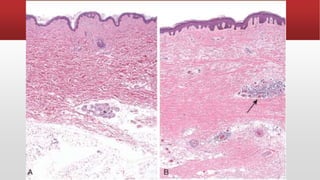

Lupus nephritis. (A) Focal proliferative glomerulonephritis, with two focal necrotizing

lesions at the 11 o’clock and 2 o’clock positions (H&E stain).

Extracapillary proliferation is not prominent in this case. (B) Diffuse proliferative

glomerulonephritis. Note the marked increase in cellularity throughout the

glomerulus (H&E stain). (C) Lupus nephritis showing a glomerulus with several “wire-

loop” lesions representing extensive subendothelial deposits of immune complexes

(periodic acid-Schiff stain). (D) Electron micrograph of a renal glomerular capillary loop

from a patient with SLE nephritis. Subendothelial dense deposits (arrowheads) on

basement membrane (arrow) correspond to “wire loops” seen by light microscopy. (E)

Deposition of IgG antibody in a granular pattern, detected by immunofluorescence.